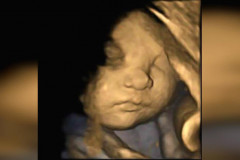

Вот как выглядят актеры любимого сериала «Великолепный век» в реальной жизни. То, что нашли в подвале старого лондонского особняка, поразило всю мировую общес... Эта девушка славится своим бюстом. Когда она сняла одежду и выключила свет, я об... Сначала я подумал, что это обычный портрет девочки. Но приглядись получше... Сергей Лазарев на "Евровидении" проводит время с 21-летней конкурсанткой из Азер... Наташа Королева и Сергей Глушко отметили годовщину отношений в бане (Фото) Знаешь ли ты, что означают эти наклейки на фруктах? Скрытый шифр тебя удивит! Она раскрыла секрет быстрого восстановления сломанного ногтя! Почему я раньше не... Натуральное средство против нежелательных волос. Нежно и без боли удаляет всё! Этот волшебный ингредиент поможет увеличить размер груди всего за несколько дней! 6 приемов, которые помогут быстро остановить кровотечение из носа Он поставил луковый компресс на шею. То, что произошло через несколько часов, — ... Как выбраться живым из тонущей машины: она вспомнила этот совет вовремя! Врачи увидели на снимке УЗИ нечто странное. Тогда мама сделала то, чего от нее н... Голь на выдумки хитра: 16 убойных примеров человеческой хитрости. Эта женщина прятала зубчик чеснока под подушку своего сына каждую ночь… Причина ... Удачный кадр (31 фото) Что будет, если в самолет ударит молния? (2 фото) В Китае родился мальчик с 31 пальцем (Фото) 23 доказательства того, что селфи придумали мужчины (23 фото) Лето стучится в дверь. Основные модные тренды предстоящего сезона (23 фото) Сестры-близнецы делают откровенные фото с игрушками, после чего продают их (13 ф... Фотограф облачает голых женщин в свет и тени (13 фото) Тот неловкий момент, когда мама и дочь выглядят на один возраст (19 фото) «Десятка» самых дорогих городов Европы 15 Голливудских Знаменитостей С Самой Неудачной Пластикой Груди Японский маникюр: 30 невероятных идей от азиатских блогеров Забавные двойные пучки: так ходит весь Голливуд! Пять вещей, которые не сделает для тебя взрослая женщина 10 трудностей, с которыми столкнется красивая женщина